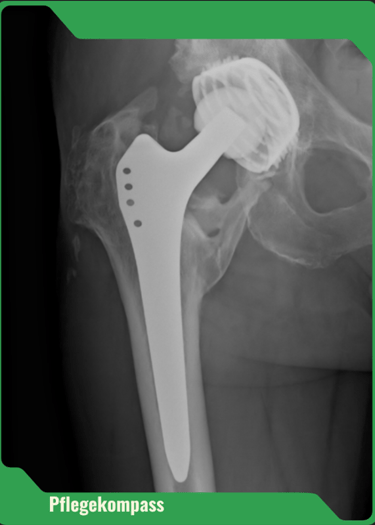

Ein Sturz bedeutet weit mehr als nur ein Ausrutschen – die Folgen reichen von Knochenbrüchen bis zum Verlust der Selbstständigkeit. Besonders häufig betroffen: der Oberschenkelhalsbruch. Über 90 % dieser Brüche entstehen durch Stürze.

Nach einem solchen Ereignis sinkt die Mobilität deutlich, und viele Betroffene können nicht mehr in ihrem gewohnten Zuhause bleiben. Deshalb ist Sturzprävention ein zentraler Bestandteil professioneller und häuslicher Pflege.

Nur 40–60 % der Betroffenen mit Hüftfraktur erreichen ihre vorherige Mobilität wieder.

Rund 10–20 % werden danach dauerhaft in Pflegeeinrichtungen aufgenommen.

Innerhalb von 6 Monaten nach einer Hüftfraktur versterben 57,8 % der Männer und 32,9 % der Frauen in Pflegeeinrichtungen.